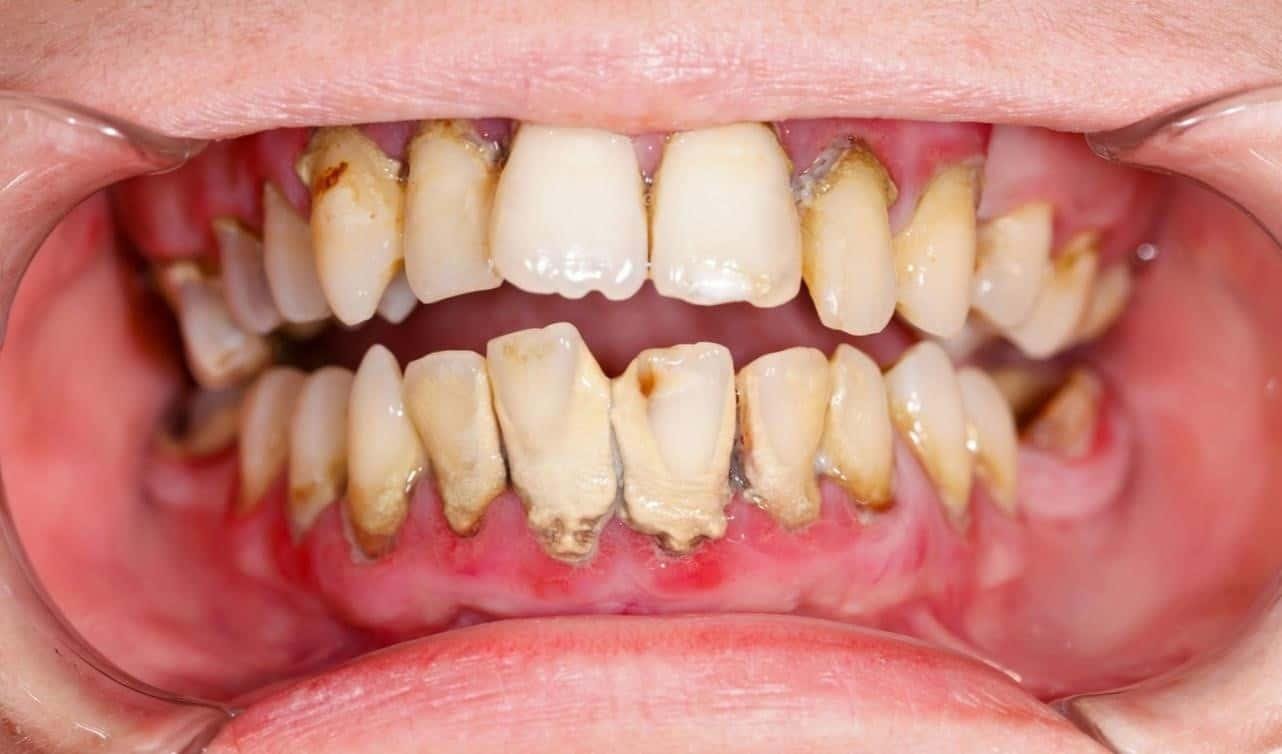

Theo nghiên cứu, có đến 80% người bị mất răng không trồng lại răng giả do nghĩ rằng có thể sử dụng các răng còn lại để ăn nhai, không quan tâm đến mặt thẩm mỹ. Tuy nhiên, mất răng gây hiện tượng tiêu xương hàm, nướu teo lại, các răng còn lại bị xô lệch. Những răng bị đổ nghiêng sẽ yếu dần, lung lay và rụng.

Toàn bộ hệ thống răng miệng bị sai lệch khớp cắn sẽ gây khó khăn trong việc trồng răng giả, phục hình răng sau này. Nhiều người thường không nhận thức đúng và không trồng răng ngay sau khi mất răng, không đề cao việc bảo tồn răng thật. Trước đây, khi bị viêm nha chu hoặc hư răng, nhiều người thường nghĩ đến việc nhổ hết răng để đeo răng giả tháo lắp, ít quan tâm đến việc điều trị giữ lại răng thật.

Hậu quả “mất răng mất lợi” – mất răng lâu năm làm tiêu xương hàm trầm trọng. Chụp phim 3D sẽ cho thấy tình trạng xương hàm, nướu teo lại, và cũng phát hiện các bệnh lý, tổn thương (nếu có).